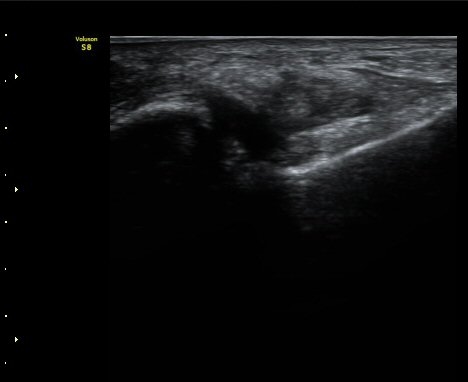

¹ß¸ñ ¾Õ Á¾´Ü¸é°Ë»ç¿¡¼­ ¹ß¸ñ°üÀý ³» ¼ö¾×Àú·ù°¡ °üÂûµÈ´Ù(±×¸² 1).